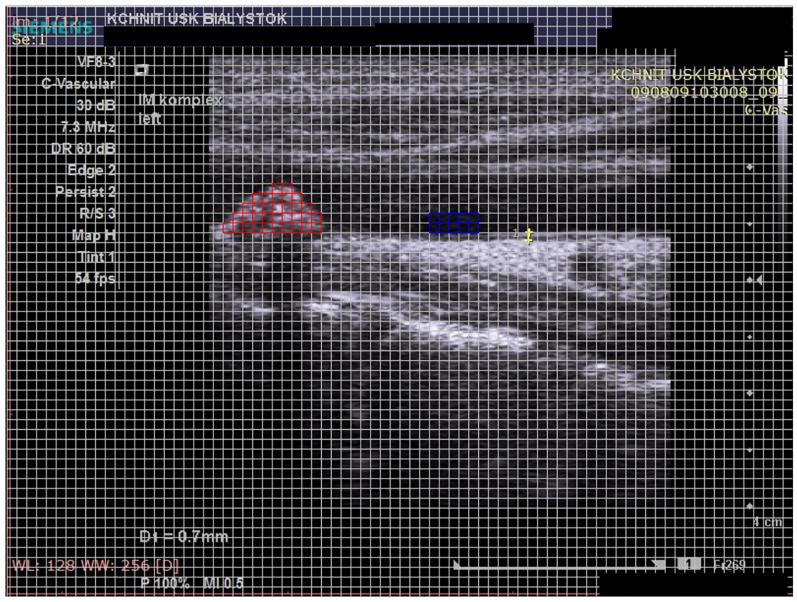

Gray-Scale Median in Patients with Symptomatic and Asymptomatic Carotid Atherosclerosis-Risk Factors and Diagnostic Potential.

This study included 45 patients with asymptomatic and 40 patients with symptomatic ICA stenosis undergoing carotid endarterectomy (CEA). Echolucency of carotid plaque was determined using computerized techniques for the GSM analysis. Study groups were compared in terms of clinical risk factors, coexisting comorbidities, and used pharmacotherapy.

Mean GSM values in the symptomatic group were significantly lower than in the asymptomatic group ( < 0.001). Both in the univariate as well as in the multiple regression analysis, GSM was significantly correlated with D-dimers and fasting plasma glucose levels and tended to correlate with β-adrenoceptor antagonist use in the symptomatic group. In asymptomatic patients, GSM was associated with the presence of grade 2 and grade 3 hypertension, and tended to correlate with the use of metformin, sulfonylureas, and statin. Independent factors for GSM in this group remained as grade 3 hypertension and statin's therapy. The receiver operating characteristic (ROC) analysis revealed that GSM differentiated symptomatic from asymptomatic ICA stenosis with sensitivity and specificity of 73% and 80%, respectively.